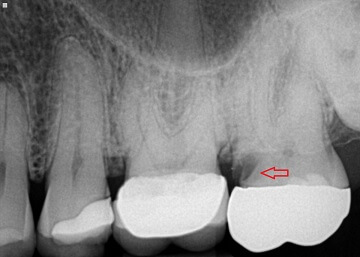

크라운 하방에 2차 충치가 생긴 x-ray 사진입니다. 빨간색 화살표를 따라가보시면 원래 흰색으로 치아가 있어야 되는 자리가 검정색으로 되어있습니다(x-ray 사진에서는 검정색이 빈공간, 흰색이 무언가 있다는 뜻입니다) 즉, 2차 충치가 생겨서 파먹은 공간(cavity)가 생긴 셈입니다. (출처: https://www.atlasdental.ca/)